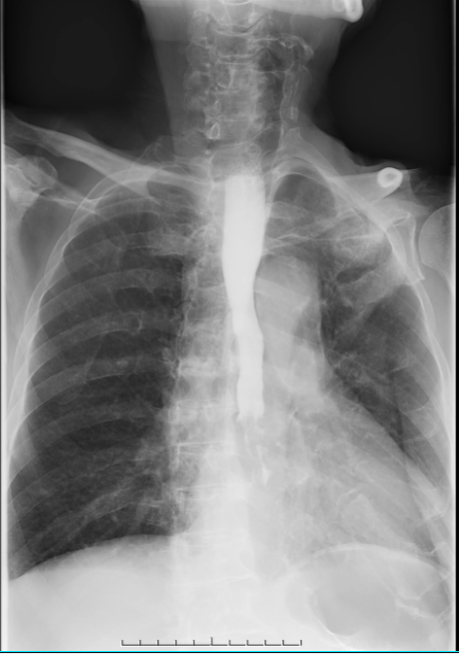

食管造影:患者食管中下段局限性狭窄